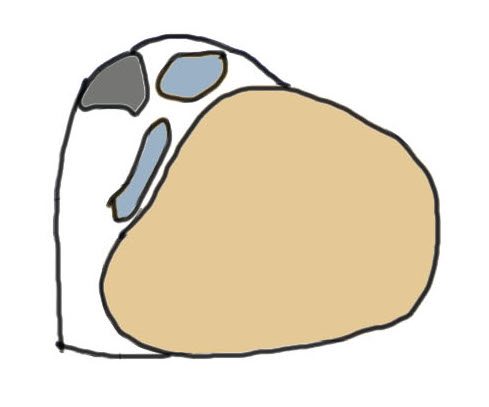

1. Injury to superior peroneal retinaculum (SPR) / fibrocartilaginous ridge (FCR)

Peroneal tendons sublux out of grove

2. Intra-sheath subluxation with intact superior peroneal retinaculum

- at surgery superior retinaculum intact with convex peroneal groove

- 10/14 had peroneal tendons switching positions

- 4/14 had a tear in PB through which PL could sublux

| SPR detaches from FCR | SPR and FCR detached | Bony avulsion of SPR and FCR | Midsubstance rupture of SCR |

Anterior subluxation of peroneal tendons

Anterior subluxation of peroneal tendons